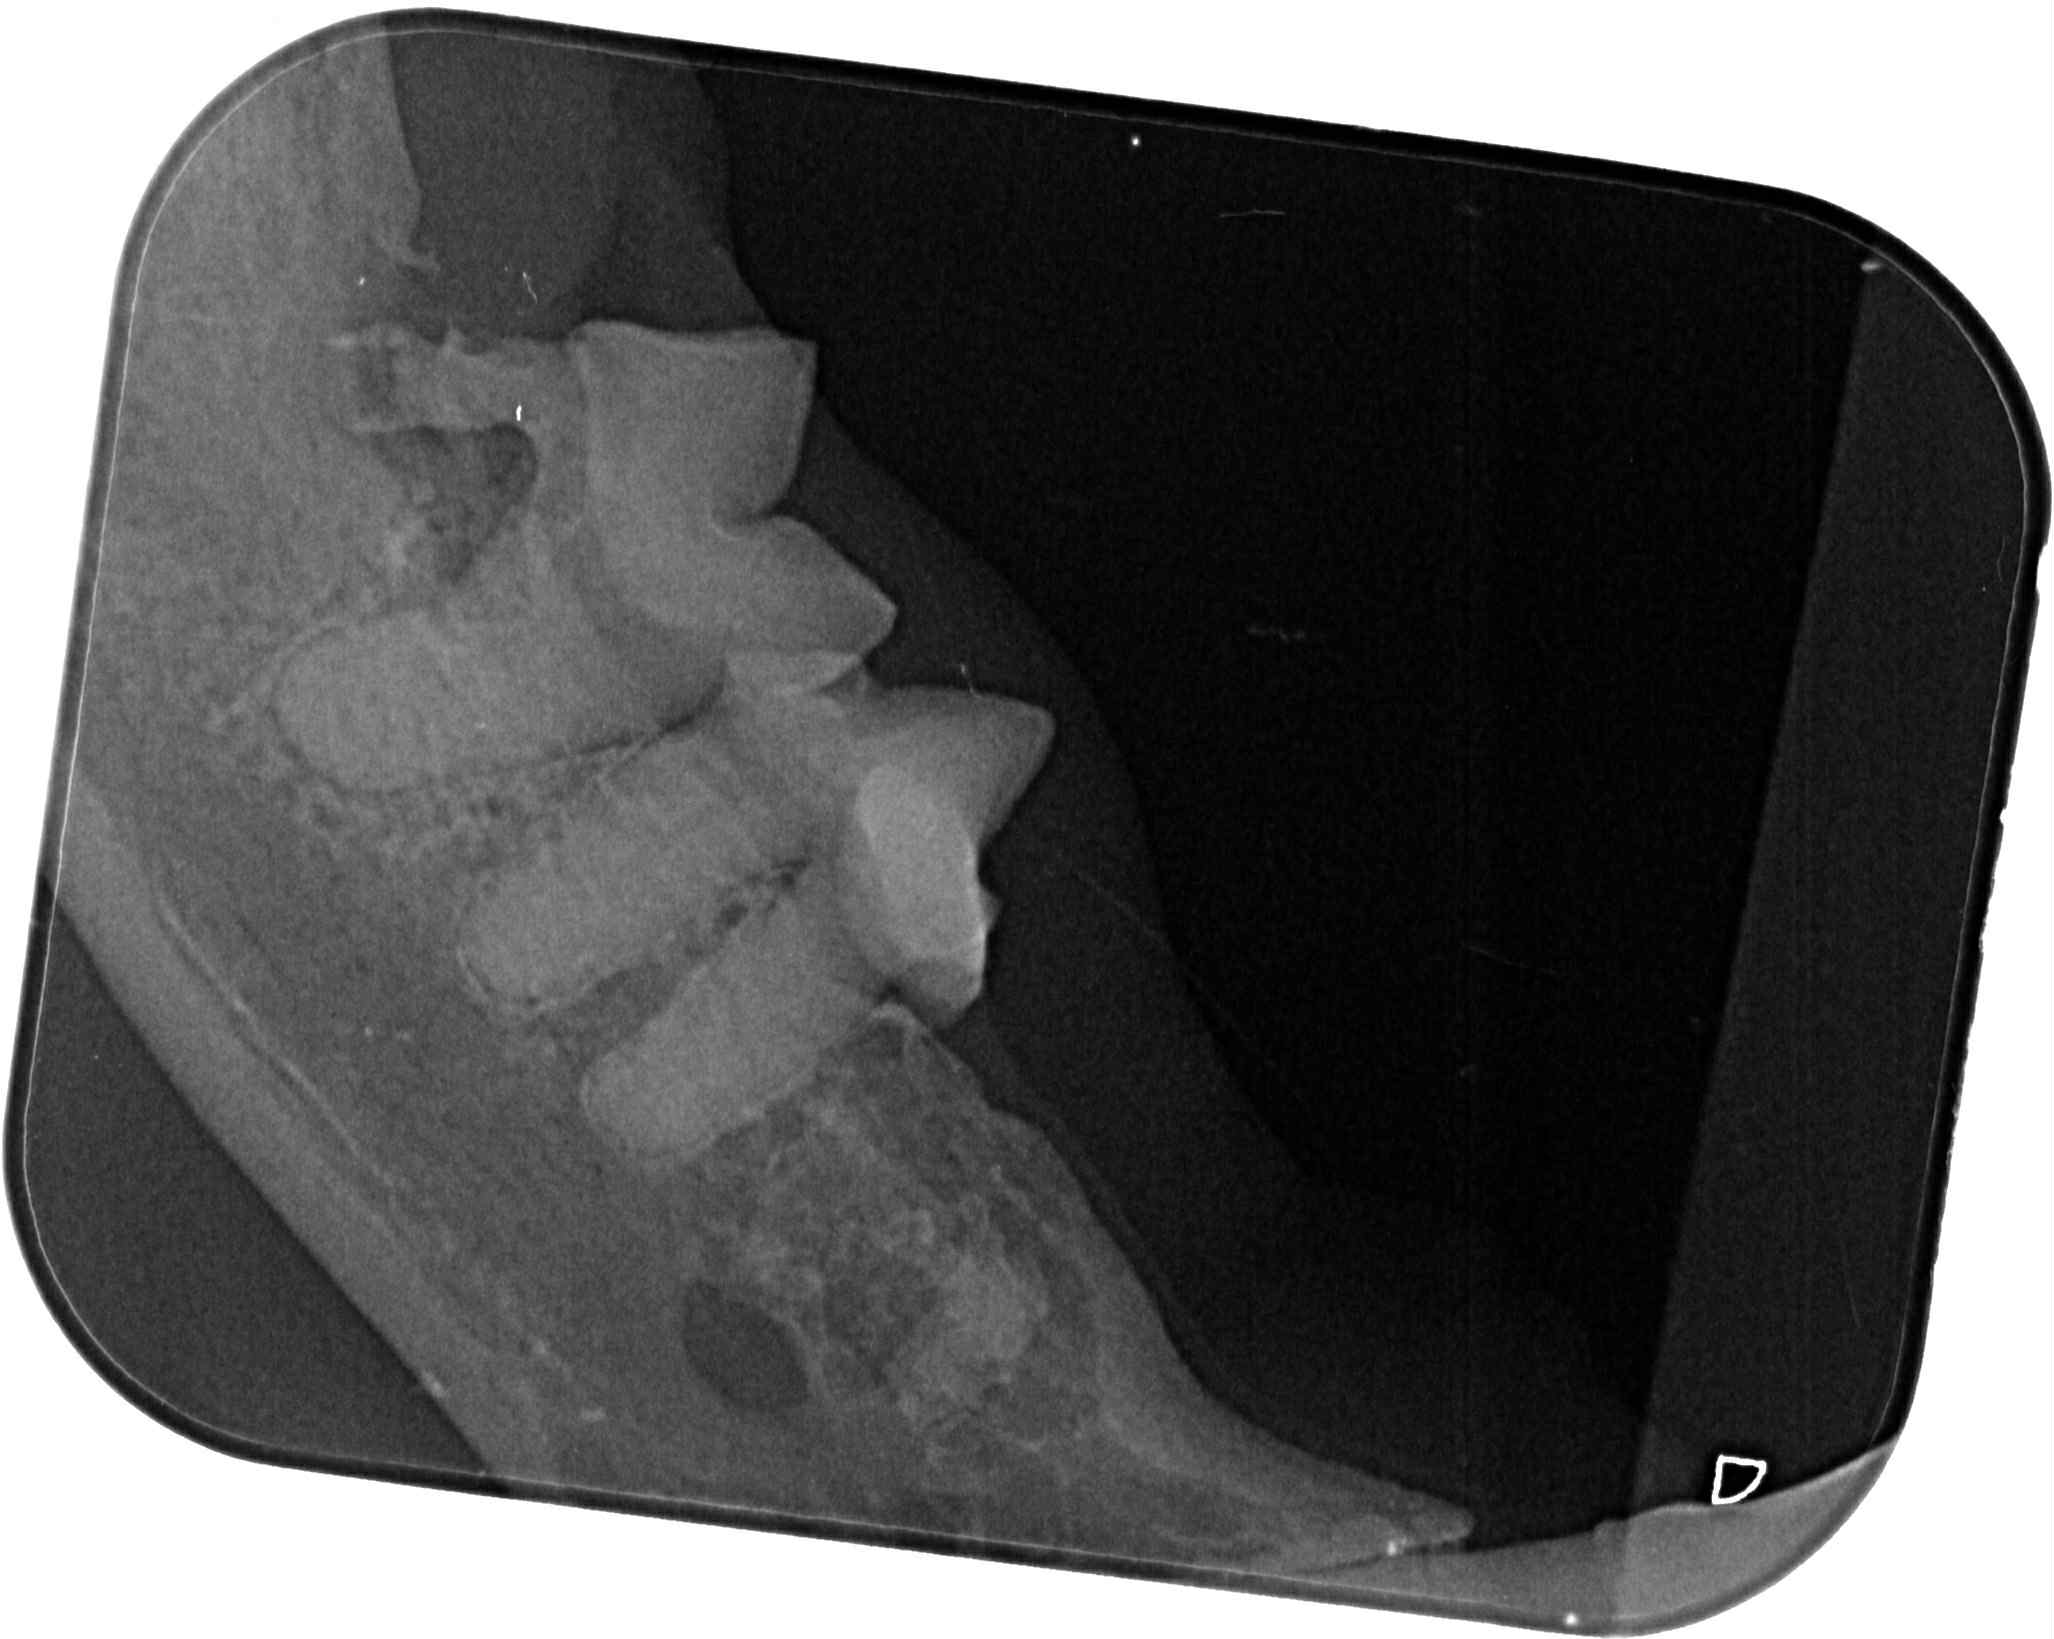

乖豹在安養之家受到良好照顧,身形越來越漂亮健美,看起來就是健康寶寶,但在2017年及2019、2020年間都突然出現無力站立、不願意走路、後肢肌肉看起來萎縮的情況,協會皆是安排乖豹至台大動物神經科專科看診,除了抽血檢驗、並將血液檢體送國外檢測重肌無力症、拍攝X光查看是否有腫瘤、核磁共振檢查及腦脊髓液採樣,查看是否腦脊髓發炎所造成的神經問題,但結果都沒有重肌無力症,也沒有找出確切原因,醫師懷疑可能是誤食含有有機磷的蟑螂藥,除了住院、吃類固醇、活性炭等用藥,照護員每天也數小時的為乖豹熱敷、按摩、復健,精神食慾有逐漸改善、走路慢慢恢復正常至痊癒,病癒後的乖豹又恢復平時的活潑調皮,在貓屋裡奔走玩耍。

原安置於苗栗貓屋的乖豹於2025年10月與其他貓咪全數移回台北安養之家後發現體型逐漸消瘦,且背上有一顆顆肉瘤以及牙齒有鬆動的狀況,於是安排2025年11月28日於沐恩看診,醫師表示整體狀況還不錯,背上粉瘤為良性,主要是牙結石嚴重,研判體重下滑應與此有關,需盡快安排牙周手術。後再於同年12月17日進行牙周手術,後面的臼齒、2顆下門牙及上顎那一顆不好犬齒都移除,保留下面兩顆犬齒,同時背部腫塊偏良性因此暫不切除。本筆醫助是自2025年11月28日至2025年12月17日間於沐恩醫院的費用,包含看診各項檢驗、牙周手術及用藥。

〔醫療〕

2025/11/28 乖豹 沐恩看診 林院長

一、看診說明

整體都不錯,主要是牙齒結石嚴重,

盡快安排時間處理,

變瘦很多應跟牙齒有關。

背部痘痘類似粉瘤但是良性,可弄牙齒時順便割掉。

2025/12/17乖豹 沐恩牙周手術

手術還算順利,血壓稍微比較不容易穩定,

目前後面的臼齒、2顆下門牙及上顎那一顆不好犬齒都移除了,

下面兩個犬齒的狀況還不錯,所以還是保留下,為了縮短麻醉時間。

皮膚的腫塊看起來外觀偏良性,所以沒切除。

目前看起來,他的咬合是比較正常的,

有可能不會咬到上顎,因為本來就已經有一邊沒有上門牙了,

理論上不會對生活有影響,另外他的下顎聯合原本就是鬆的,

所以會一個伸縮的彈性,對上顎影響相對減少

下顎聯合鬆的意思就是兩側下顎骨會些微的上下晃動。